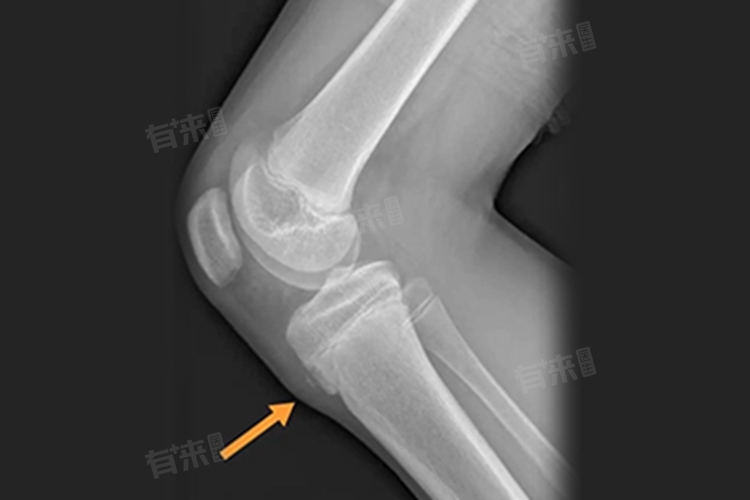

- 在青少年时期,胫骨结节骨骺尚未完全骨化,剧烈运动或过度使用膝关节,会使髌腱反复牵拉胫骨结节骨骺,引发炎症反应。此过程主要局限在胫骨结节局部,并不直接干扰长骨骨骺板的正常生长机制。

- 而长高主要依赖于长骨两端骨骺板软骨细胞的不断增殖、骨化,只要骨骺板未闭合,人体就有长高可能,如股骨、胫骨等长骨的骨骺板在正常生理状态下,按自身节奏进行生长活动,胫骨结节骨骺炎通常不波及关键的长高部位。

- 需要注意的是,若胫骨结节骨骺炎长期未得到有效治疗,炎症持续存在,可能会引起局部骨质增生、骨骺异常骨化等情况。虽然这种情况少见,但一旦发生,有可能影响胫骨的正常生长形态,进而对下肢长度产生一定影响,间接影响身高。